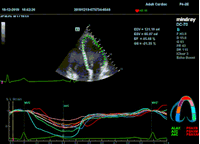

Всё изменилось с появлением технологии Speckle-tracking. Ультразвуковые приборы компании Mindray DC 8, 70, 80, Resona 6,7 оснащены данной функцией. Для использования необходим ЭКГ-канал. В чем же смысл данного технологического новшества? Прибор использует видео петли сечений миокарда, разбивает миокард на точки со стабильной визуализацией – speckle, и затем производит слежение каждой точки в течении нескольких сердечных циклов. Изменение пространства между точками дает нам представление о возможностях деформации миокарда, как продольной – Longitudinal Strain, так и деформации скручивания – торсии и Radial Strain.

Как работать с данным методом? Для Longitudinal Strain необходимо записать видео петли апикальных сечений в память прибора: 4С, 3С, 2С. Для повышения качества трекинга рекомендуется производить запись на выдохе пациента. Затем произвести разметку по линии эпикарда, перикарда и центра миокарда. Нажатием кнопки «начать слежение» активируется программный алгоритм, видео петля оживает вместе с размеченными точками-speckle’ами. При необходимости производится коррекция. После анализа всех трех сечений можно получить данных продольной деформации как в среднем значении, так и по каждому сегменту миокарда левого желудочка. Нормальным показателем считается Longitudinal Strain -20%. Нижней границей -14%.

Видео примеры на приборе Mindray DC 70